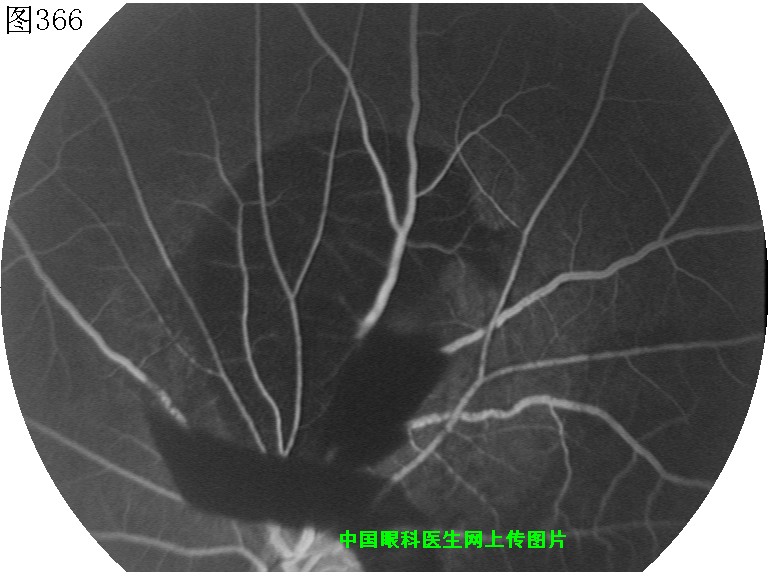

365 366 367 368